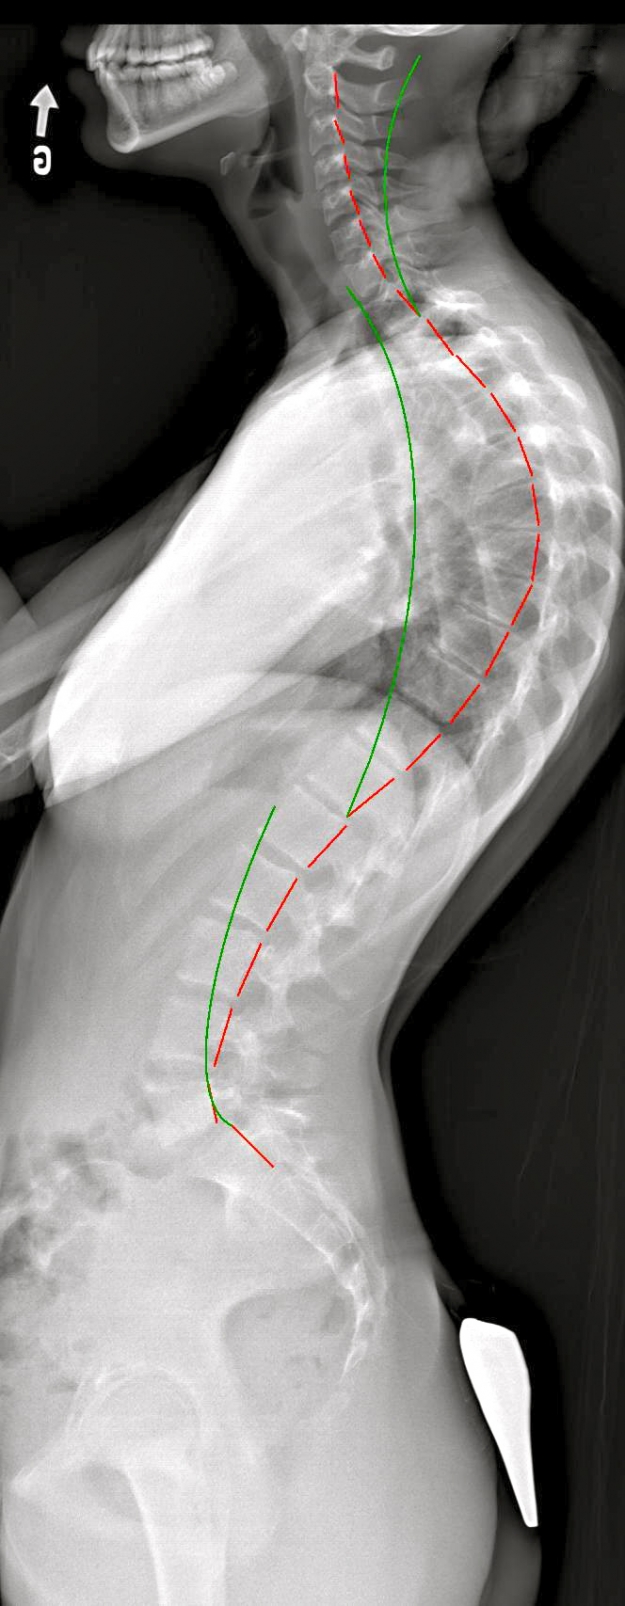

Hyperkyphosis without brace |

Hyperkyphosis with brace |

Profile X-rays of an adolescent patient with hyperkyphosis. The green line represents the ideal spinal curve and the red line follows the patient's spine. In the second X-ray, where the patient is wearing the SpineCor® brace, a significant reduction of the abnormal curve can be observed in the thoracic region, associated with a dramatic improvement of the lumbar curve.